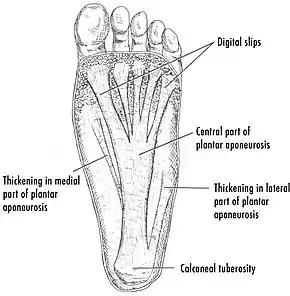

The cause of plantar fasciitis is poorly understood and appears to have several contributing factors.[15] The plantar fascia is a thick fibrous band of connective tissue that originates from the medial tubercle and anterior aspect of the heel bone. From there, the fascia extends along the sole of the foot before inserting at the base of the toes and supports the arch of the foot.[3][11][13]

Disruptions in the plantar fascia's normal mechanical movement during standing and walking (known as the Windlass mechanism) place excess strain on the calcaneal tuberosity and seem to contribute to the development of plantar fasciitis.[15] Other studies have also suggested that plantar fasciitis is not due to inflamed plantar fascia, but may be a tendon injury involving the flexor digitorum brevis muscle located immediately deep to the plantar fascia.[13]

The plantar fascia has three fascicles-the central fascicle being the thickest at 4 mm, the lateral fascicle at 2 mm, and the medial less than a millimeter thick.[18] In theory, plantar fasciitis becomes more likely as the plantar fascia's thickness at the calcaneal insertion increases. A thickness of more than 4.5 mm ultrasound and 4 mm on MRI are useful for diagnosis.[19] Other imaging findings, such as thickening of the plantar aponeurosis, are nonspecific and have limited usefulness in diagnosing plantar fasciitis.[13]